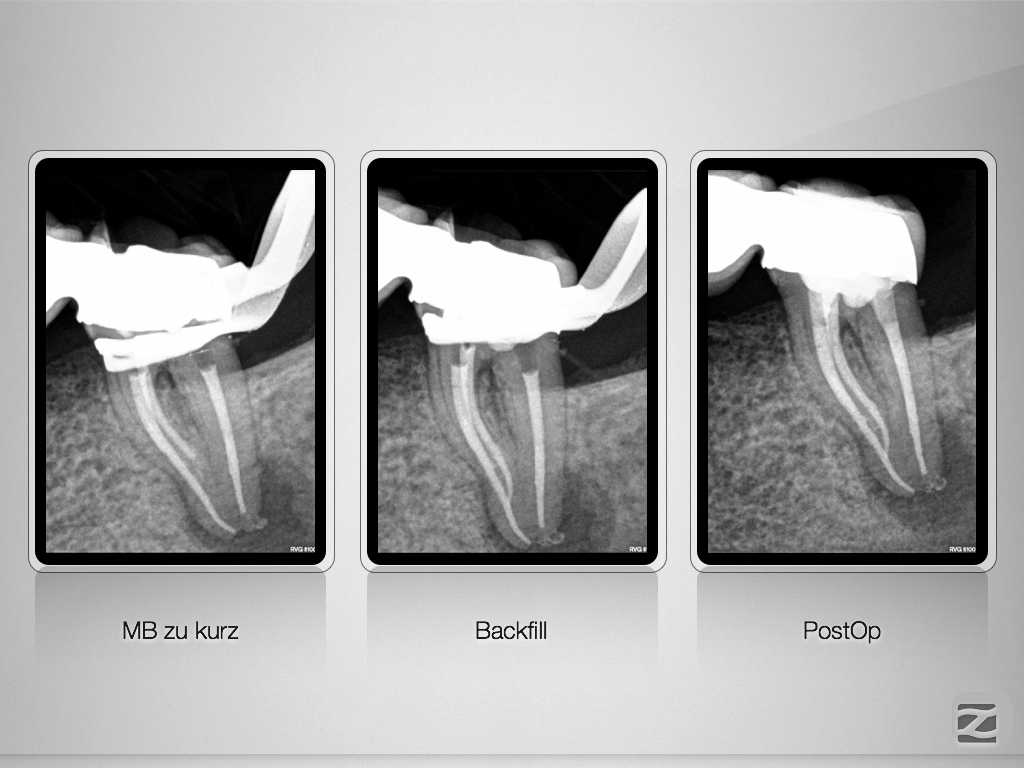

37D.008

Recall einer ausgedehnten apikalen Lyse